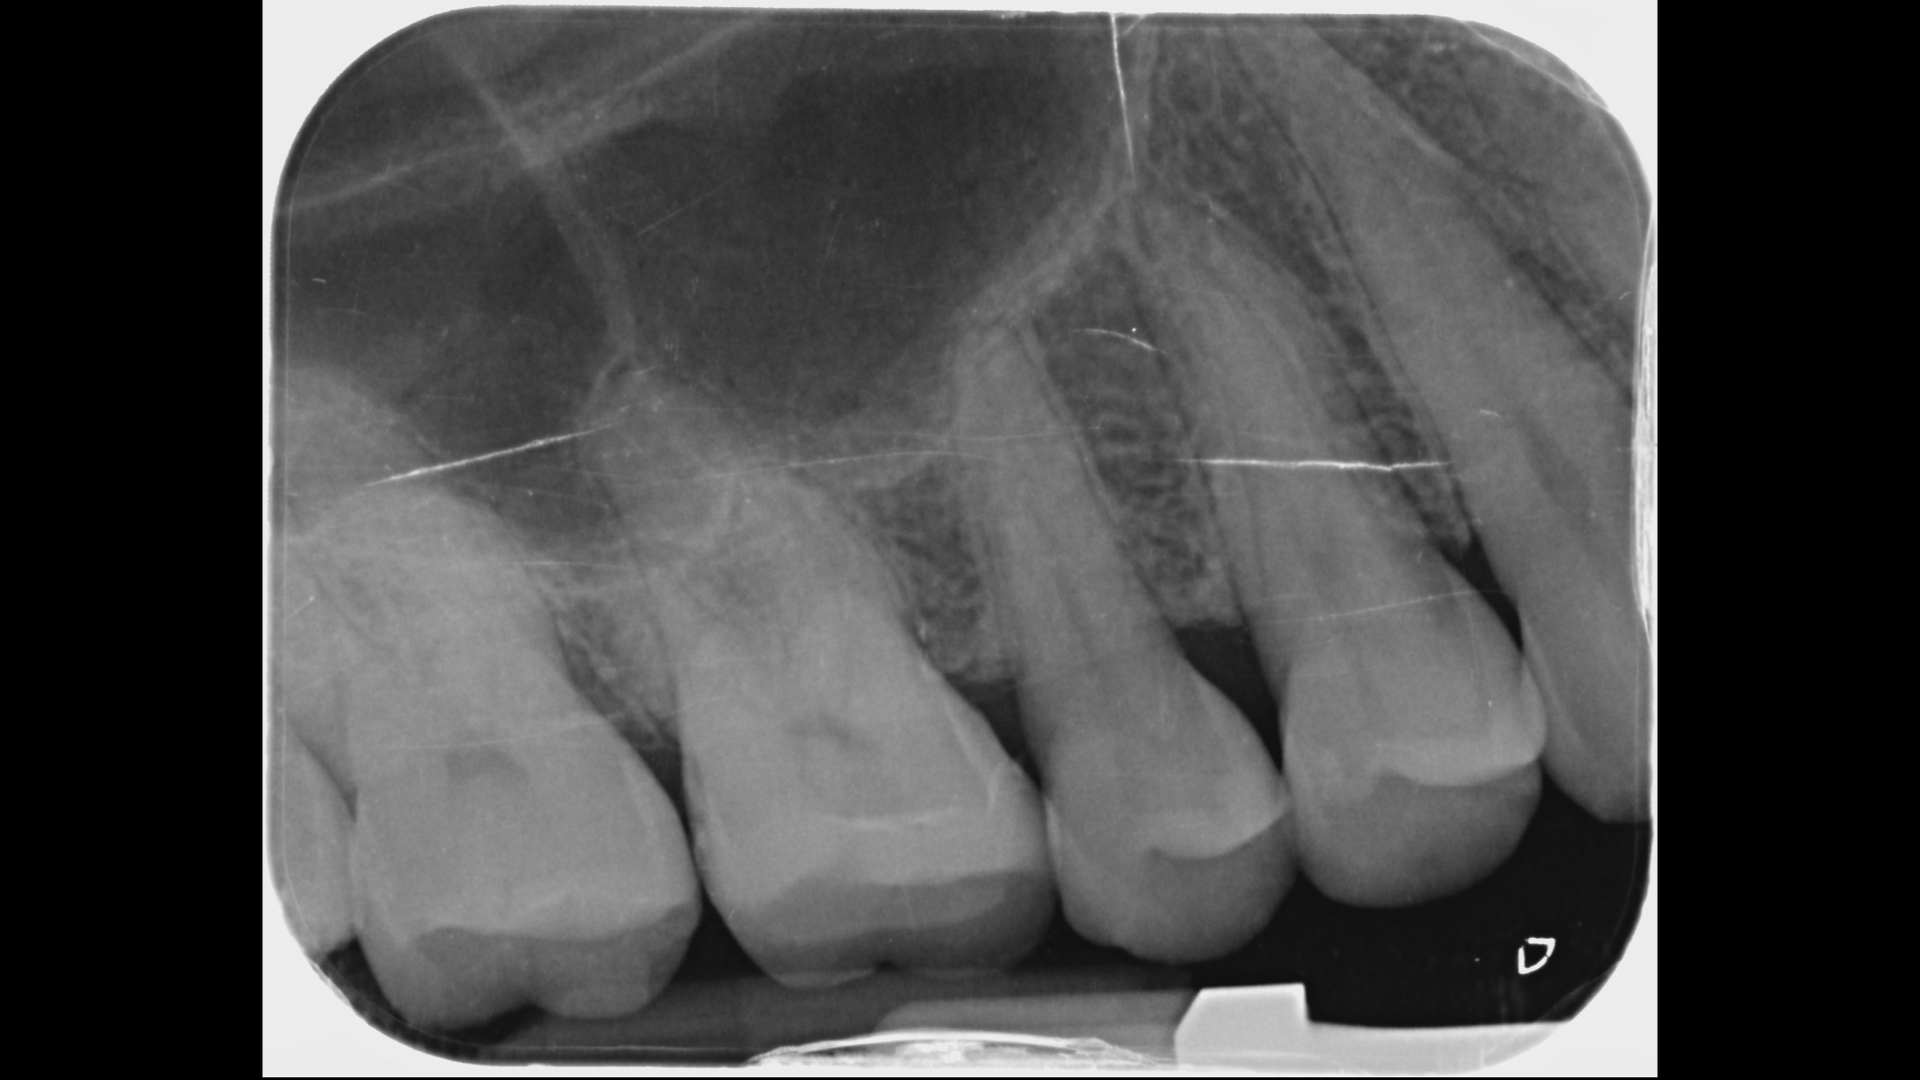

X光發現裂痕延伸到接近骨頭